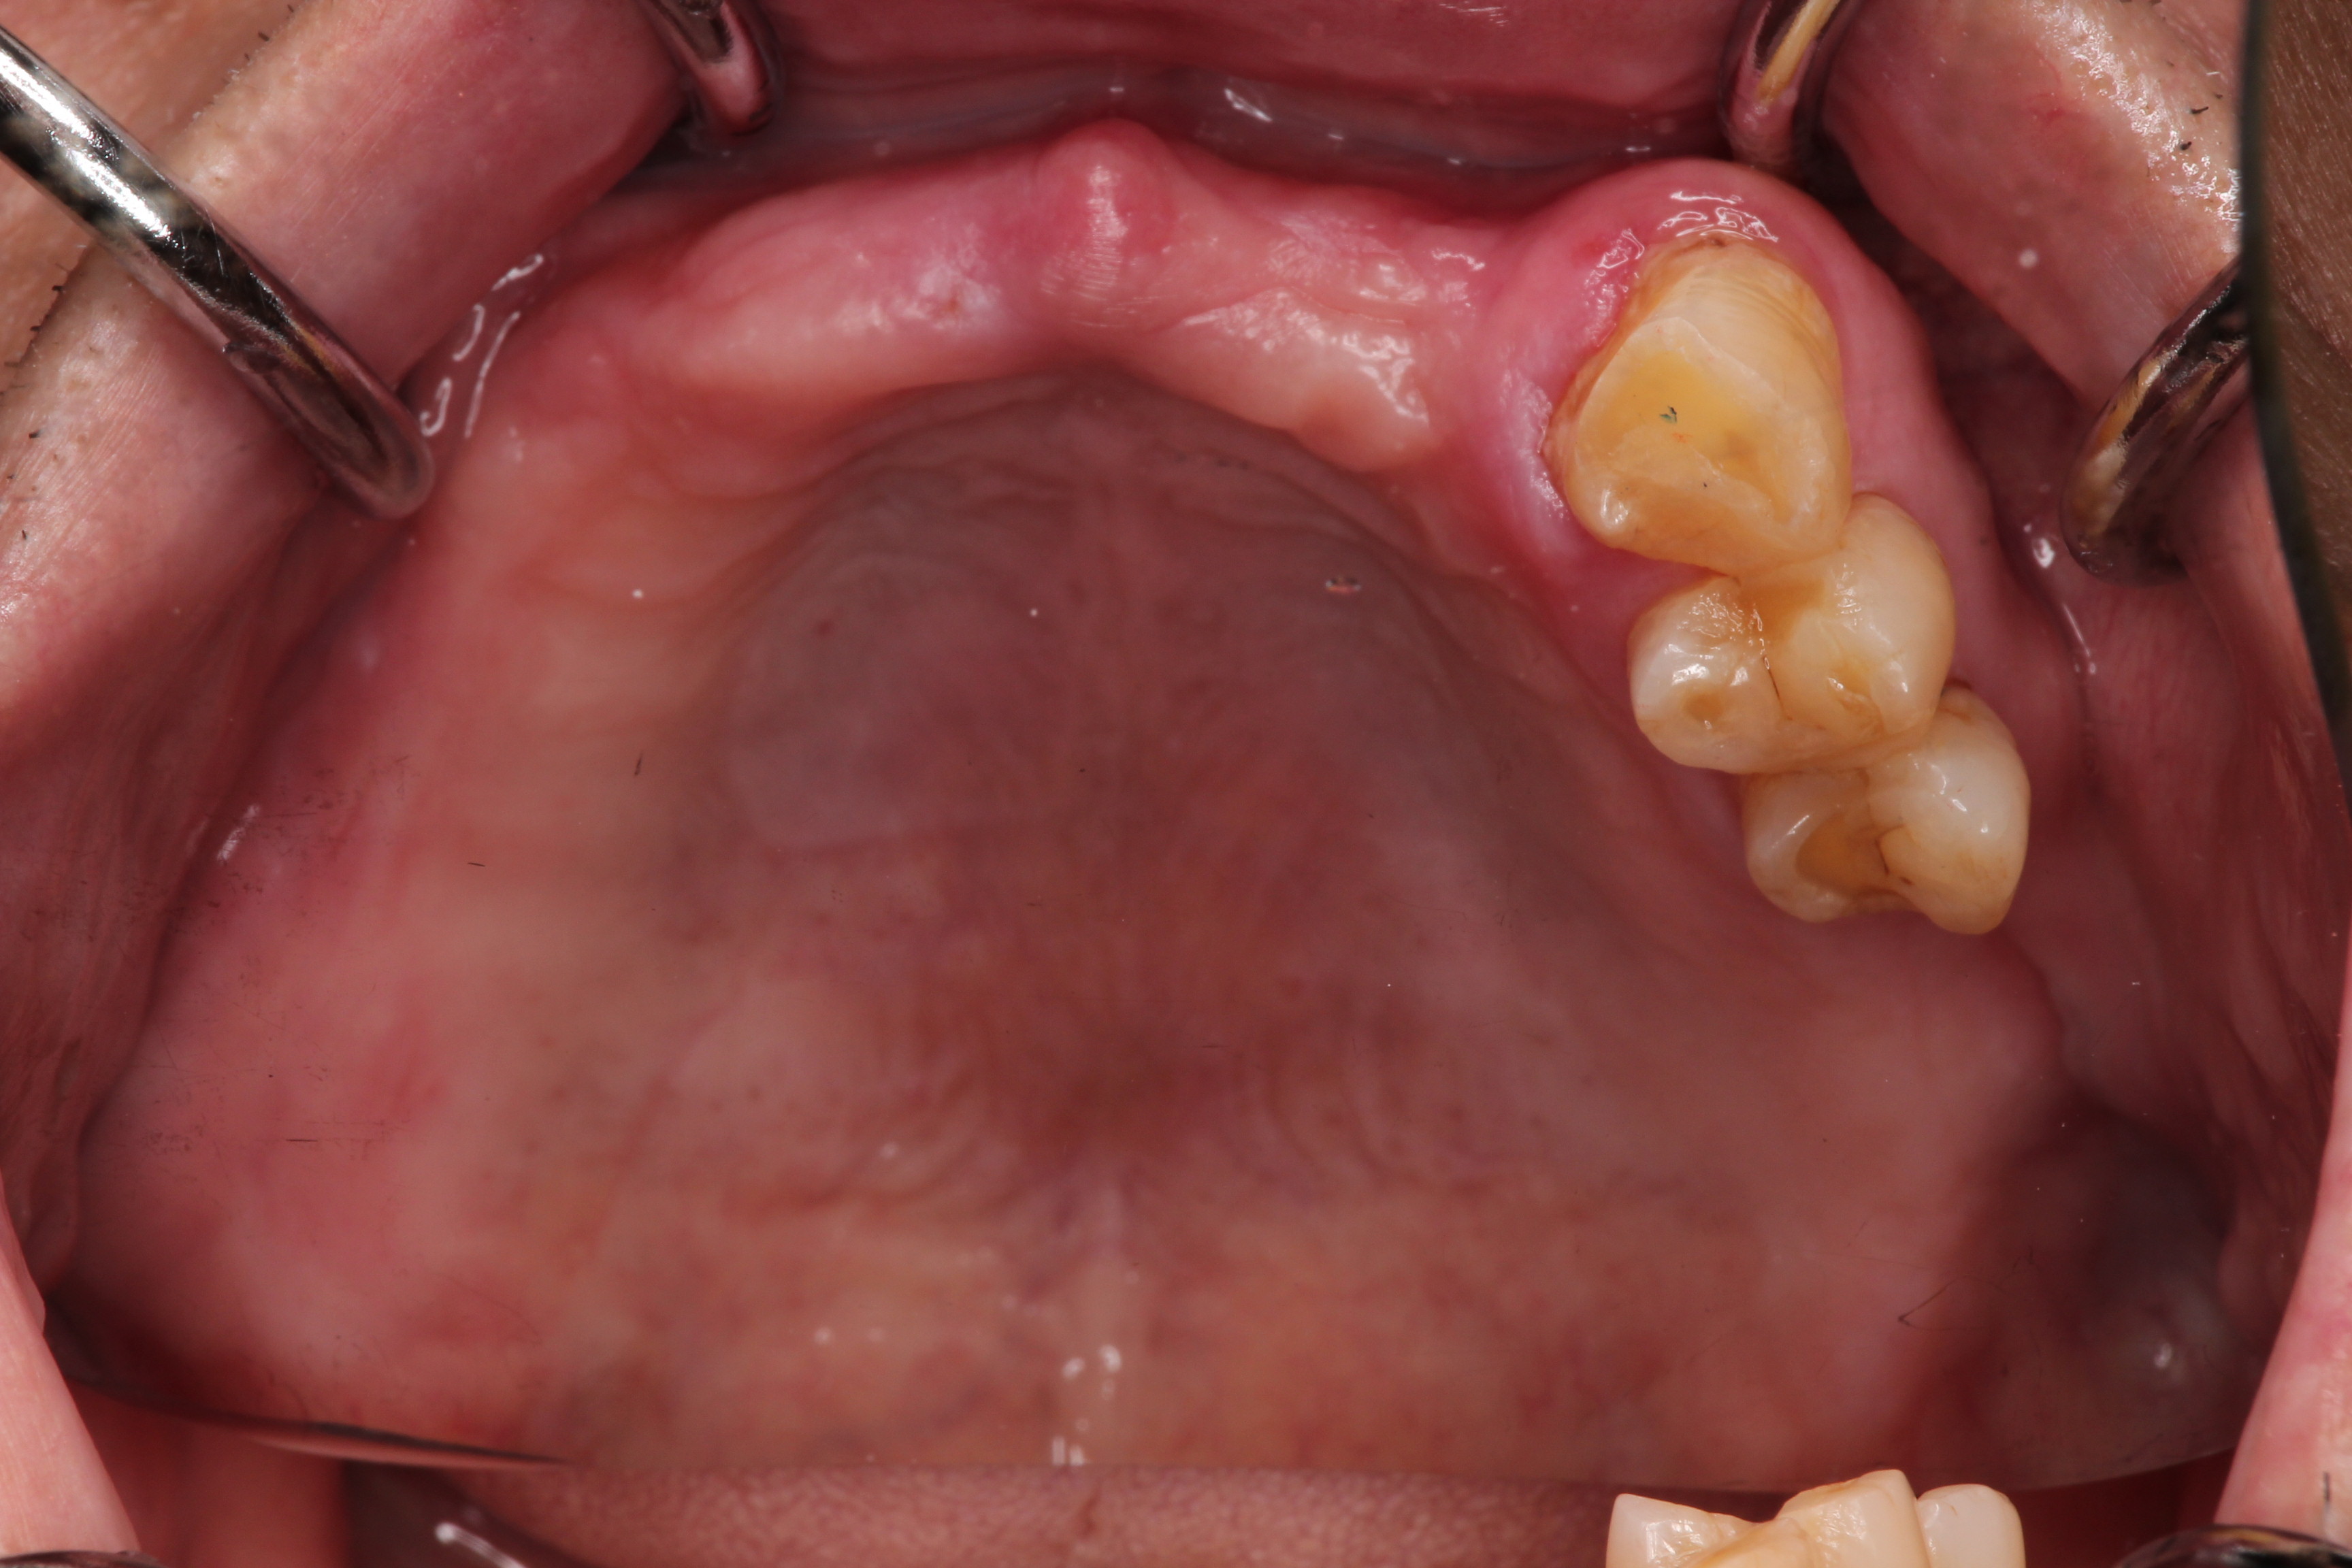

こちらは歯と歯に囲まれた欠損(中間欠損)となりますのでKennedy Ⅲ級となります。